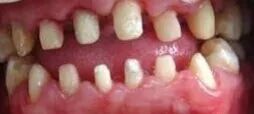

如果说烤瓷桥和全口烤瓷美容修复只是一个时代的象征,本质上不是忽悠的话,那么,另一种烤瓷牙方式——“美容冠”,则是彻头彻尾的大忽悠!首先,无论口腔医学本科教材,专科教材还是研究生教材,都没有美容冠这一概念,医院和正规牙科诊所都没有这项业务,它是纯粹的商业包装的产物,只存在于美容院等等医美机构,一般都以“七天正牙美容冠”,“纳米仿生美容冠”等等诱人的字眼吸引患者尤其是女学生,其操作流程是将患者不整齐的牙齿磨小或齐牙龈截断,通过套上烤瓷牙或全瓷牙达到牙列整齐美观的效果。

这些患者本来可以接受矫正治疗,既不伤牙髓又不用戴假牙,可得到既健康又长久而且自然的美学效果,却被美容院那些全无口腔执业医师证的美容师们忽悠。美容师都是抓住患者嫌矫正太慢急于求美的心情,而避谈美容冠的各种弊端,最终坑了那些花季少女。而被忽悠的她们,也成为后期在网络上各贴吧烤瓷吧里对烤瓷牙声泪控诉的绝对主力,因各种并发症而到口腔科检查时那种“恨不相逢未治时”的哀怨声几乎从未绝于耳。